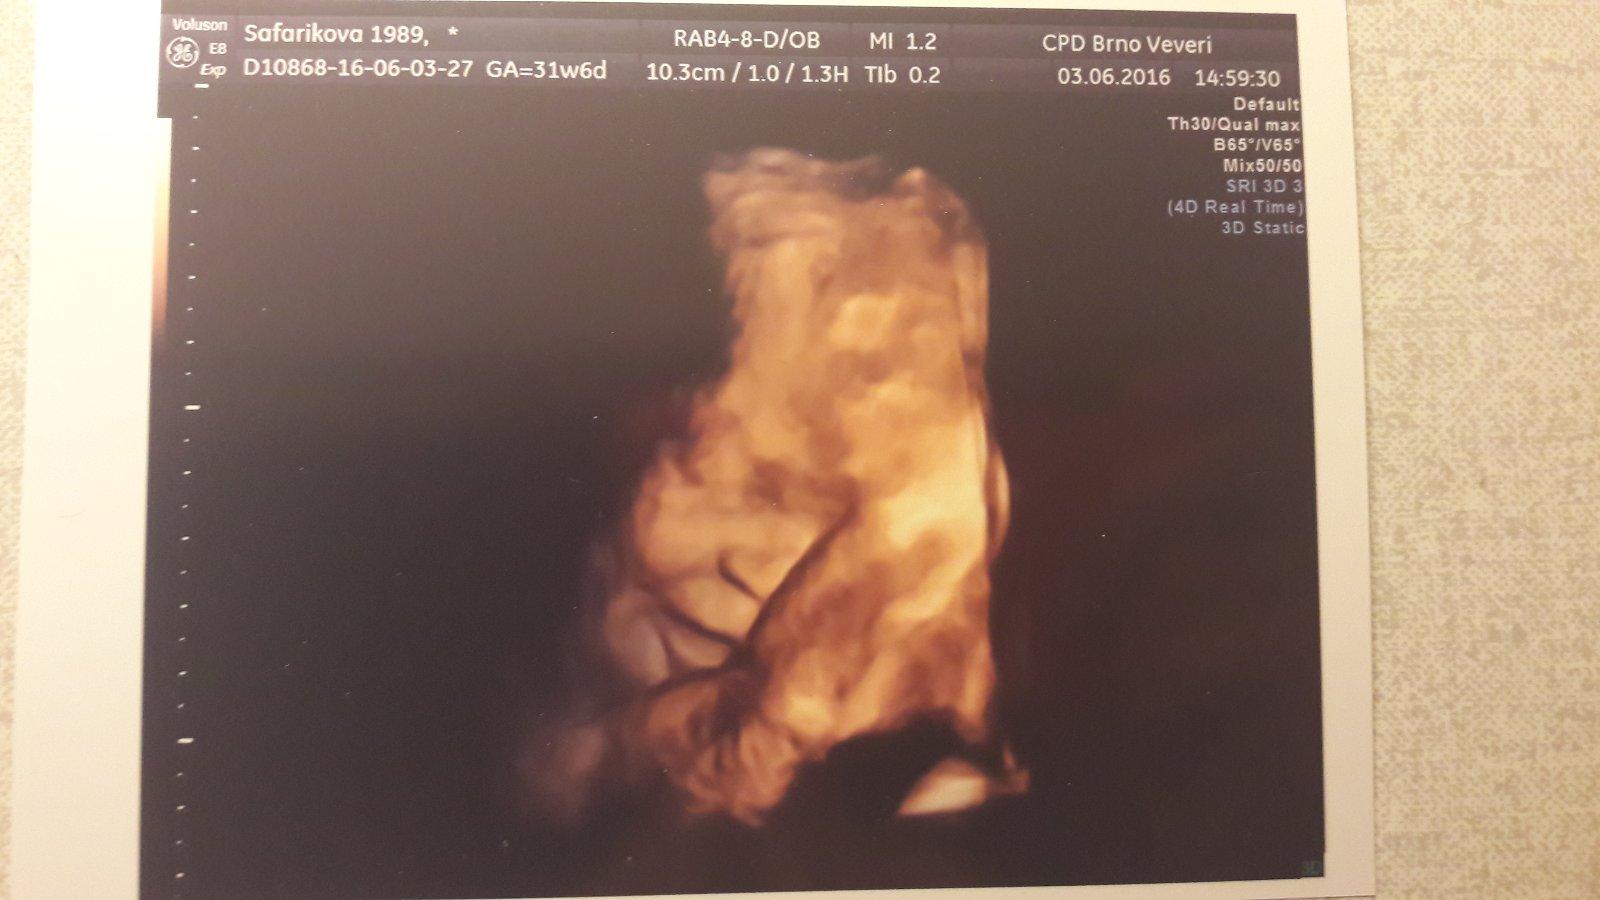

slunicko156 : Ahoj, ja u nej byla na e.ultrazvuku a parada 🙂 Byla jsem nejspokojenejsi ze vsech navstev, byl moc ochotny a mily. Chteli jsme barevnou fotku za 200Kc, jako delali vzdycky (proste klasicka z ultrazvuku akorat na fotopapire a barevna), ale on nam to prepnul do 3D a jeste udelal nekolik variant, abysme si vybrali 🙂 A byla taky za 200Kc, byla jsem nadsena!

@safarikovag Ahoj, u prvního UTZ si musíme říct o fotku sami nebo nám ji udělají automaticky? A platí se taky 200kč? Moc děkuji za odpověď

@ruzena90 O fotku si musis rict (myslim, my si rikali vzdycky), barevna stoji tech 200Kc, cernobila min, tusim kolem 50Kc 🙂

@ruzena90 pokud jdeš na prvotrimestrální screening, tak si ho platíš a v ceně máš fotečku (černobílou), já ji dostala automaticky, ani jsem si nemusela říkat .. 🙂 u dalších, které jsou hrazené už se platí a musíš si říct .. Mají to i přímo na stránkách: "Všechny maminky u nás dostanou jako pozornost k vyšetření i obrázek svého miminka a podrobnou zprávu o vyšetření , včetně našeho dalšího doporučení. " http://www.prenatal.cz/index.php?id=57